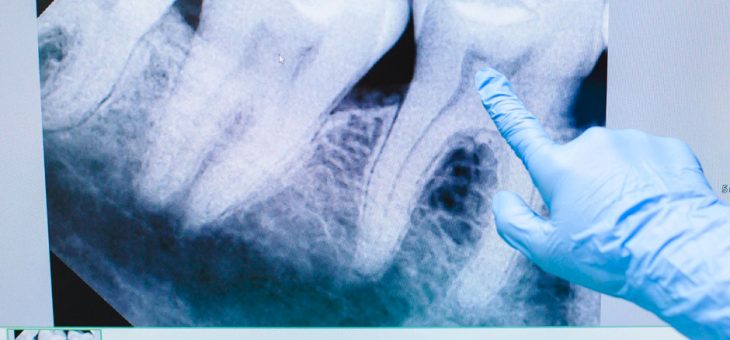

El TAC dental es una prueba diagnóstica que brinda al especialista muchos más detalles que una radiografía convencional, pues arroja imágenes en 3D. Desde Gadir Dental te contamos para qué se utiliza, sus ventajas y riesgos. No hay que confundir el escáner dental o TAC dental, siglas que corresponden a ‘Tomografía Axial Computarizada’, con unaLeer más sobre TAC dental: tu boca en 3D[…]